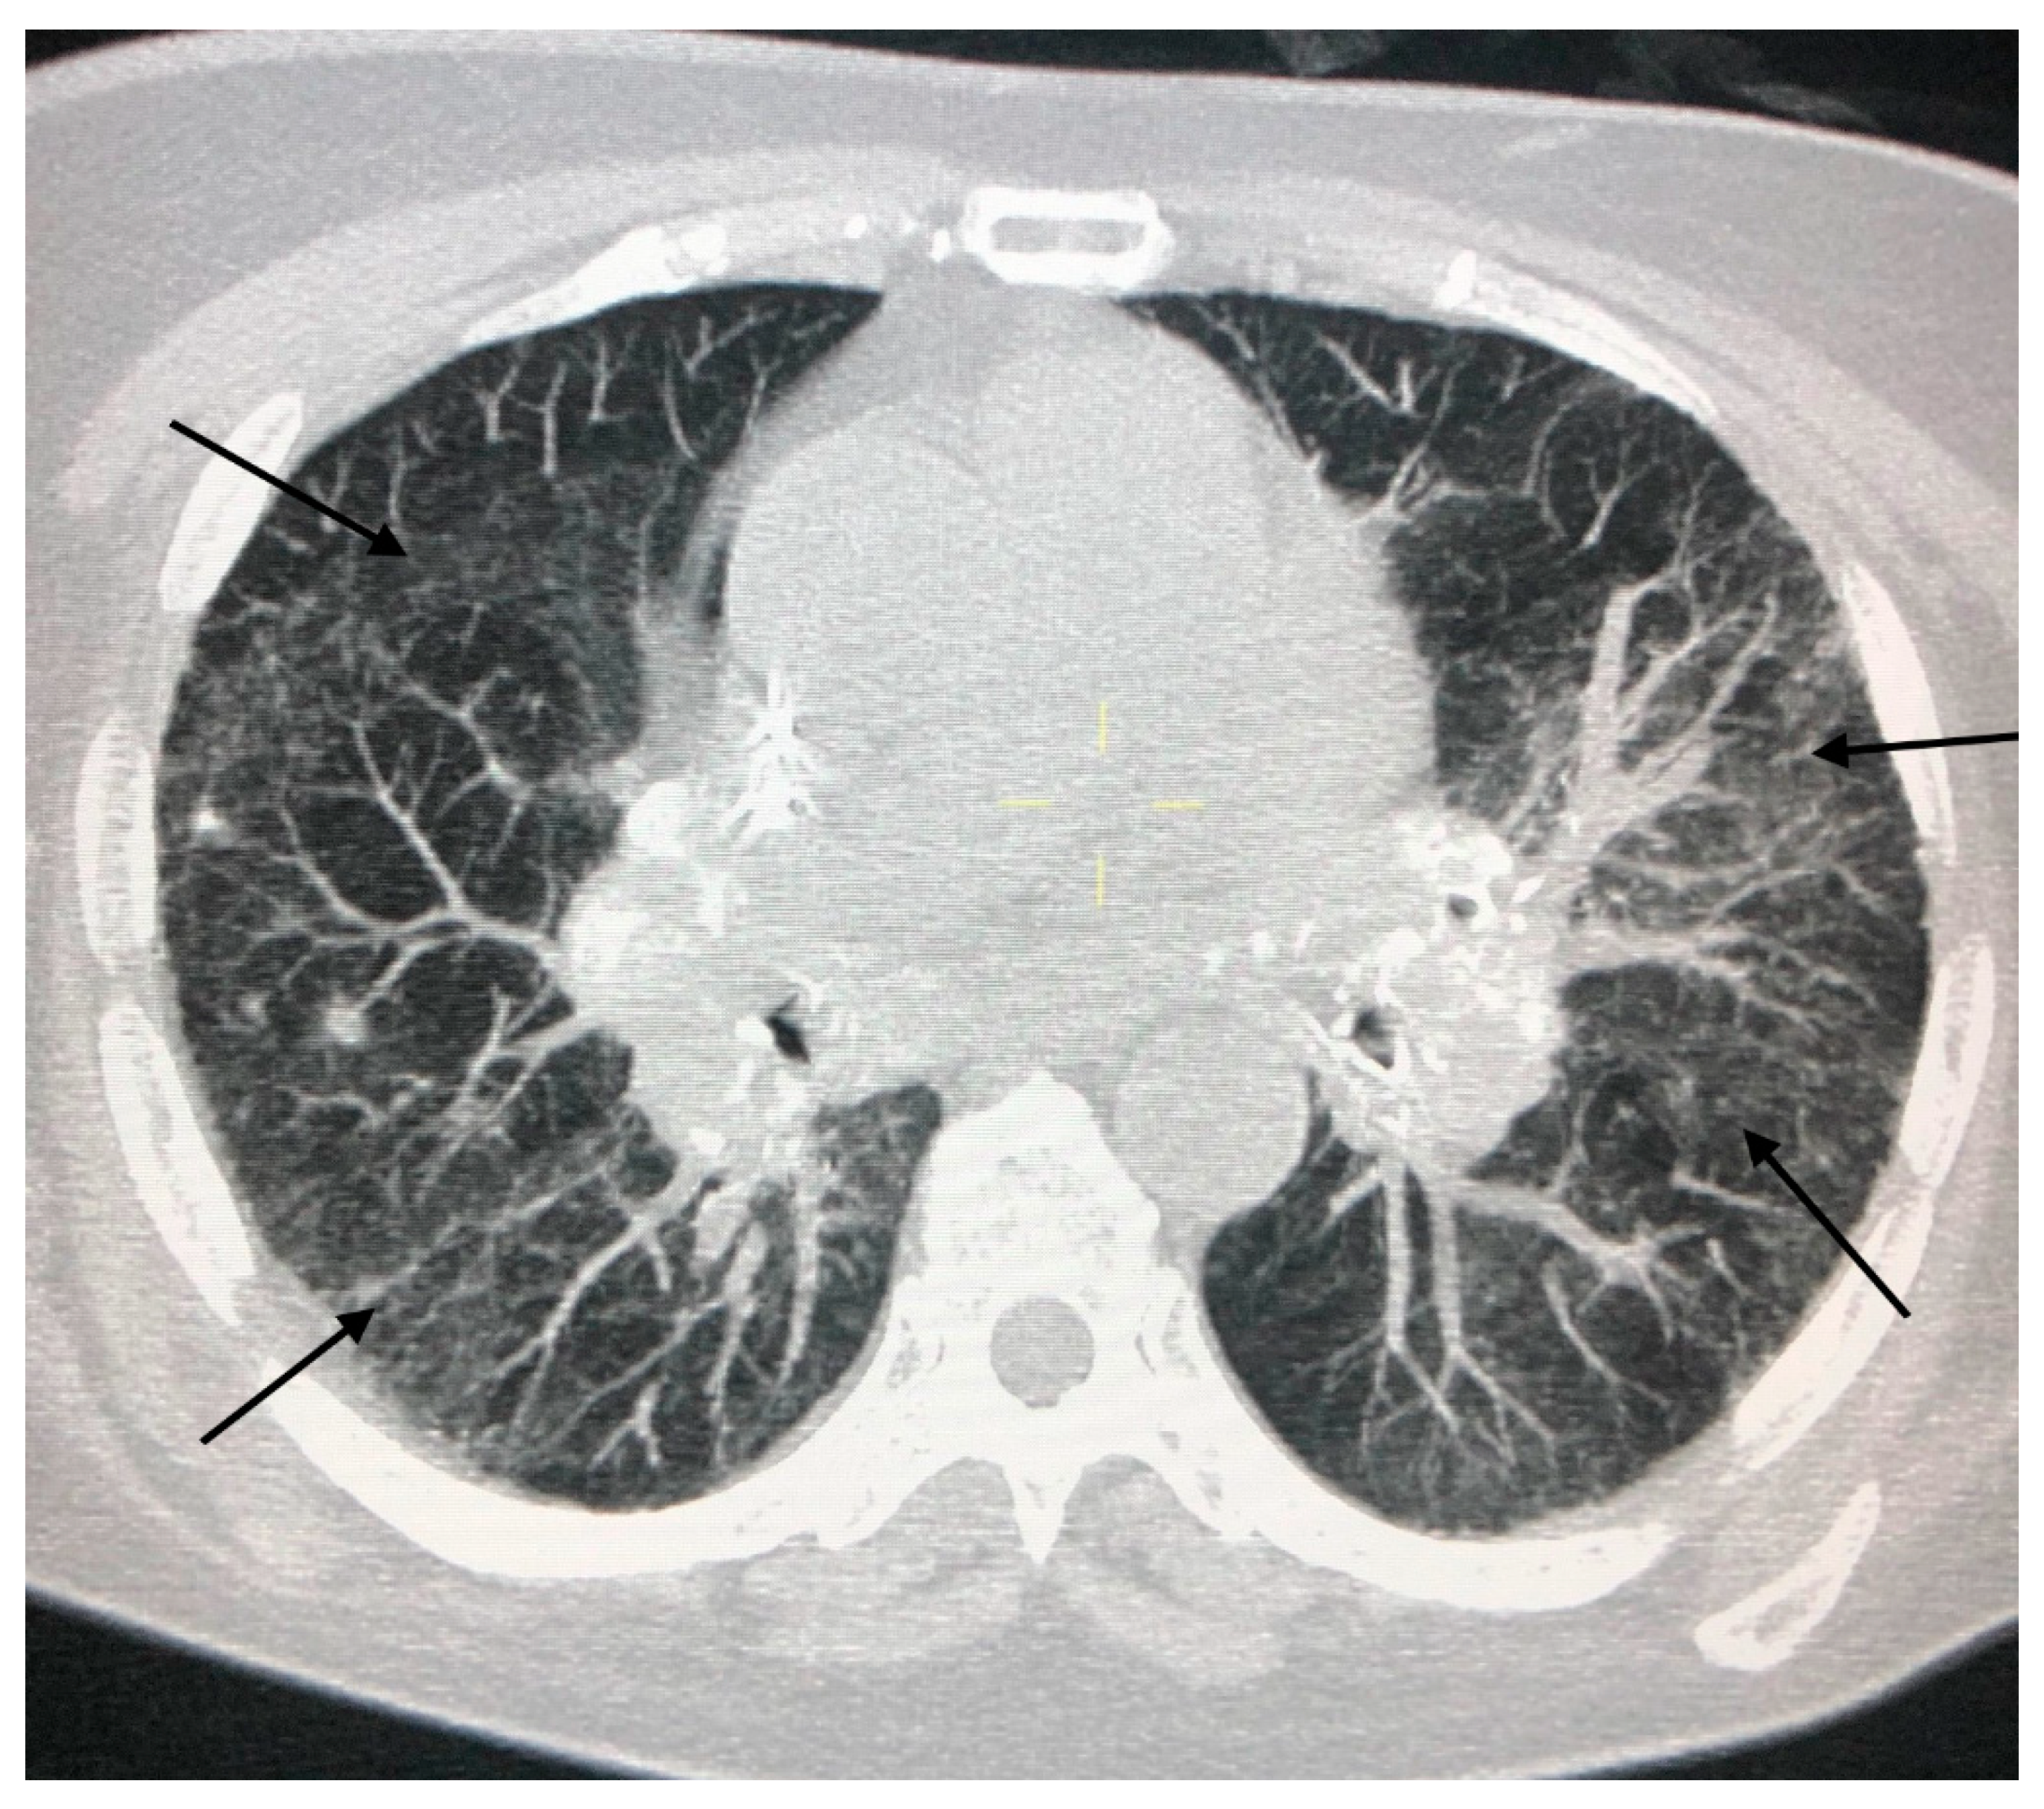

3. CT in Pulmonary Sarcoidosis, Imaging Findings and Classification